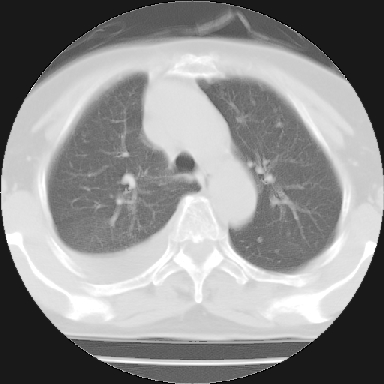

以下是引用苯小孩在2007-4-13 16:20:00的发言:[br]1、右下肺中央型肺癌并阻塞性肺不张、肺内转移、胸椎右侧附件亦有转移<横断层面第8层>.[br]2、右侧胸腔积液.

以下是引用swyyy2007在2007-4-13 15:31:00的发言:[br]右肺门下区肿块,右肺下叶支气管阻塞,右肺下叶不张,右侧大量胸腔积液,右肺中叶见结节状高密度影,边缘清,纵隔内见肿大淋巴结。首先考虑右下肺中心型肺癌伴右肺下叶不张、中叶、纵隔淋巴结转移。右侧胸腔积液。